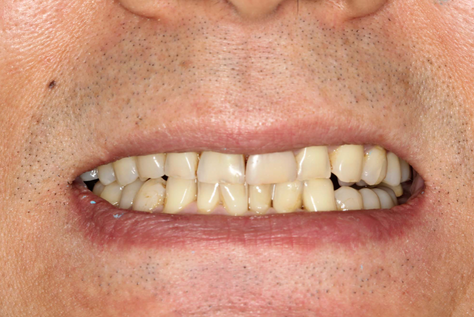

Mr NK, a 52-year-old male, presented with concerns of gradually shortening teeth and sensitivity to cold drinks. He also reported feeling self-conscious about his smile in photos. He is medically fit and has been using a night guard for his sleep-related grinding habit for the past year. Clinical examination revealed moderately worn dentition from erosion and attrition, along with mild crowding of the lower anterior incisors.

Intra-Oral Pictures (Before)